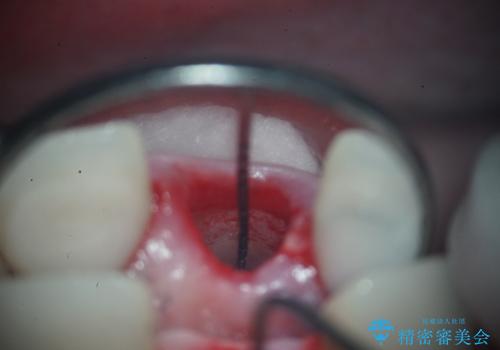

- 治療計画

- 前歯の痛みと破折を主訴にご来院されました。精密な診査の結果、歯の根元までひび割れが進行し、保存が困難であると診断。見た目にも関わる前歯を失うことへの患者様の不安を考慮し、抜歯と同時にインプラントを埋入する抜歯即時埋入インプラントによる治療計画を立案しました。これにより、歯がない期間を最小限に抑え、治療期間と身体への負担を軽減しながら、審美性の高い新しい歯を獲得することを目指します。

今回の治療では、まず原因となっていた前歯を慎重に抜歯し、その直後にインプラントを埋入しました。抜歯即時埋入は、歯を失うのとほぼ同時に新しい歯の土台を確保できるため、骨の吸収を防ぎ、仕上がりの美しさを保つ上で非常に有効です。また、治療当日に仮歯を装着することで、歯がない期間をなくし、患者様の精神的なご負担にも配慮しました。最終的に、周囲の歯と調和したオーダーメイドのセラミッククラウンを装着。機能性だけでなく、天然歯と見分けがつかないほどの自然で美しい前歯を取り戻していただけました。